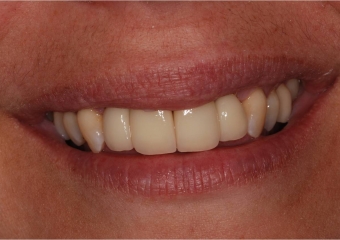

Dentes individuais em porcelana

Sorriso final, do caso terminado em abril de 2013